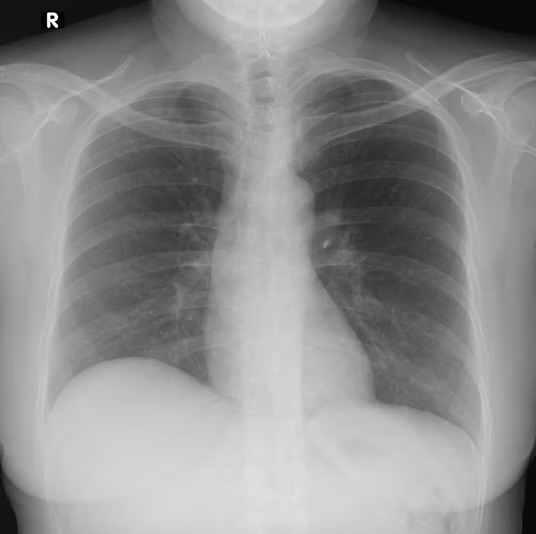

Para determinar si la penetración de una radiografía frontal de tórax es adecuada, se emplea un criterio práctico y ampliamente aceptado: la visualización de los cuerpos vertebrales dorsales a través de la silueta cardiaca. En condiciones óptimas, los contornos de la columna vertebral deben percibirse de manera tenue pero definida detrás del corazón. Esta observación indica que el haz de radiación ha sido suficiente para atravesar tanto las estructuras óseas posteriores como el tejido cardiaco y mediastínico, sin comprometer el contraste necesario para evaluar el parénquima pulmonar. Si las vértebras no son visibles a través de la silueta cardiaca, es probable que la imagen esté subpenetrada. Si, por el contrario, se observan con excesiva nitidez y el pulmón aparece muy oscuro, puede sospecharse una sobrepenetración.

La penetración radiográfica constituye un determinante fundamental de la calidad diagnóstica en la radiografía frontal de tórax, ya que condiciona la representación fiel de las relaciones de densidad entre las distintas estructuras torácicas. Cuando la energía del haz de rayos X es insuficiente para atravesar adecuadamente los tejidos, se produce una imagen globalmente más clara, fenómeno que corresponde a una atenuación excesiva de la radiación antes de alcanzar el detector. En términos prácticos, se considera que existe penetración insuficiente cuando no es posible distinguir los cuerpos vertebrales dorsales a través de la silueta cardiaca. Esta incapacidad de visualizar la columna posterior indica que el haz no ha tenido la energía necesaria para atravesar de manera equilibrada las estructuras mediastínicas y óseas, alterando el contraste natural entre los tejidos.